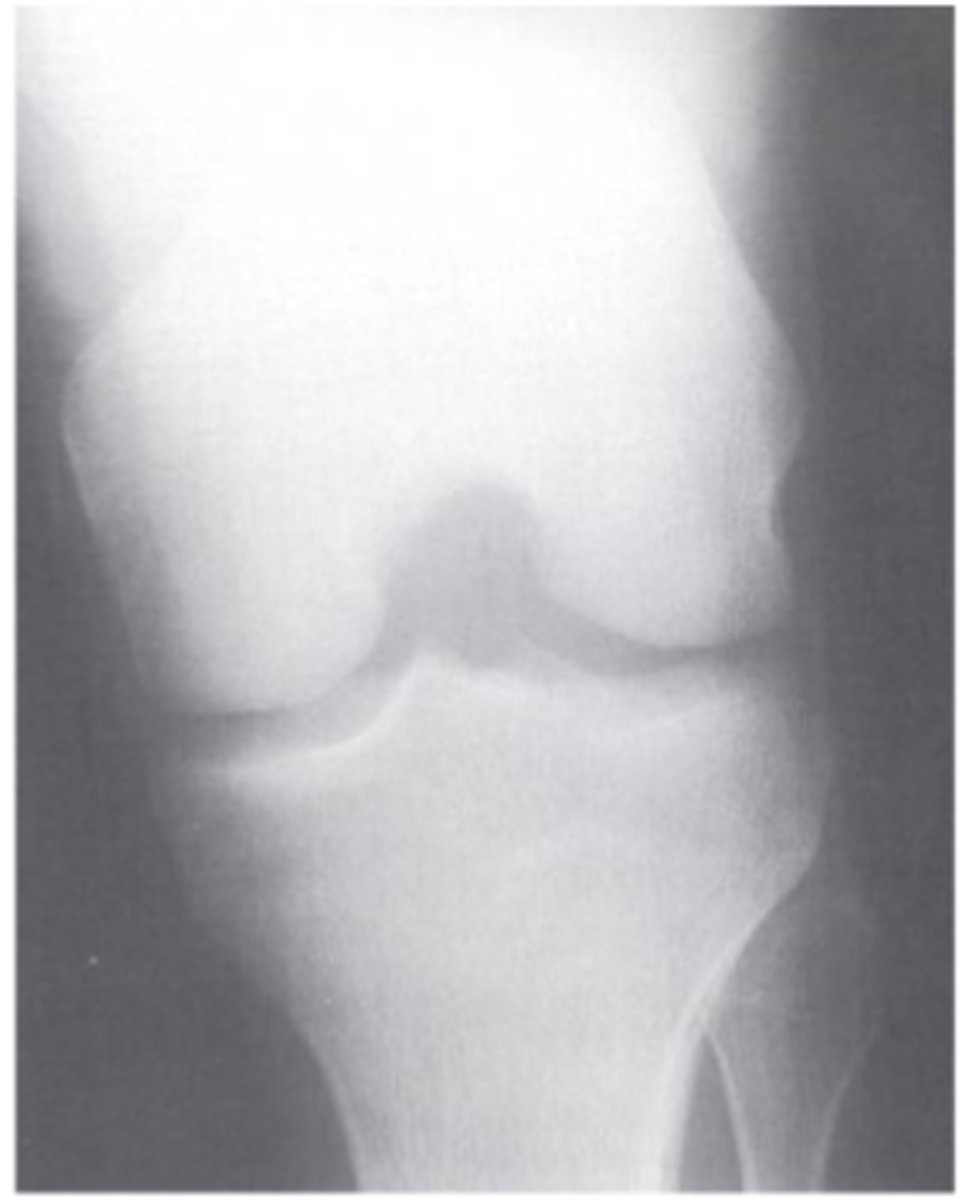

Tunnel AP view with knee flexed

What view does this show?